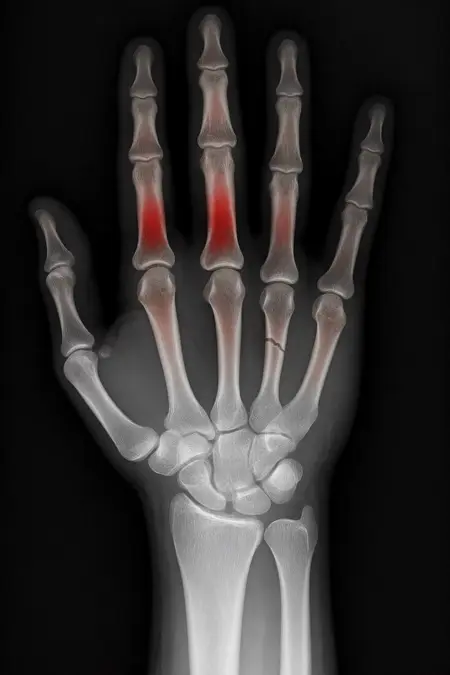

アートや写真の編集用に設計されたFlux Kontextのようなモデルを、医療画像、たとえば「単純な」骨折の赤色マーキングに使用できるか?

即答:面白い結果を出すが、過剰に反応し、医療ツールとしては信頼性に欠ける。これはアイデアを試すためのプロトタイプに過ぎない。

テスト結果:

- 偽陽性 ≈ 24%

- 骨折検出 ≈ 20%

感度モード(検出を優先、ノイズ多め)

- Euler、15ステップ、Karras

- Denoise:1.0

結果:

- 偽陽性 ≈ 80%

- 骨折検出 ≈ 86%

さらに攻撃的な設定(例:rk beta57、Denoise 1.0)では、**偽陽性100%、検出100%**という馬鹿げた結果に:すべてを赤で塗りつぶし、健常部もほぼすべて骨折と誤認する。未経験の目には区別がつかない。

Civitai用に作成した、100% AI生成の合成ミニデータセット(健康なX線10枚、骨折のあるX線10枚)でテスト:

- 健康な骨での偽陽性:100%

- 骨折検出:≈ 45%